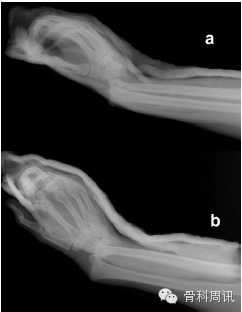

一名35歲男性從大約5米的高處墜落後,摔傷其右上肢,送往我院急診室就診。體格檢查顯示腕部銀叉樣畸形,所有手指無法正常屈伸,並且第一、二、三根手指均出現感覺喪失。橈動脈搏動不明顯。X光片顯示橈骨遠端骨折伴腕骨從尺骨遠端背側脫位(圖1)。在麻醉狀態下嚐試采取閉合複位術。複位失敗後,進行CT掃描檢查。CT顯示,橈骨莖突骨折和橈骨遠端粉碎性骨折伴腕骨背側移位和腕骨近端骨折移位。下尺橈關節顯示穩定(圖2)。由於複位失敗,所以采取手術治療。

Fig. 2. Axial (a and b) and sagittal(c and d) CT images showing dorsally and proximally displaced radiocarpal fracture dislocation.

圖2 顯示背側和近端移位的橈腕關節骨折脫位的軸向(a and b)和矢狀(c and d) CT圖像。